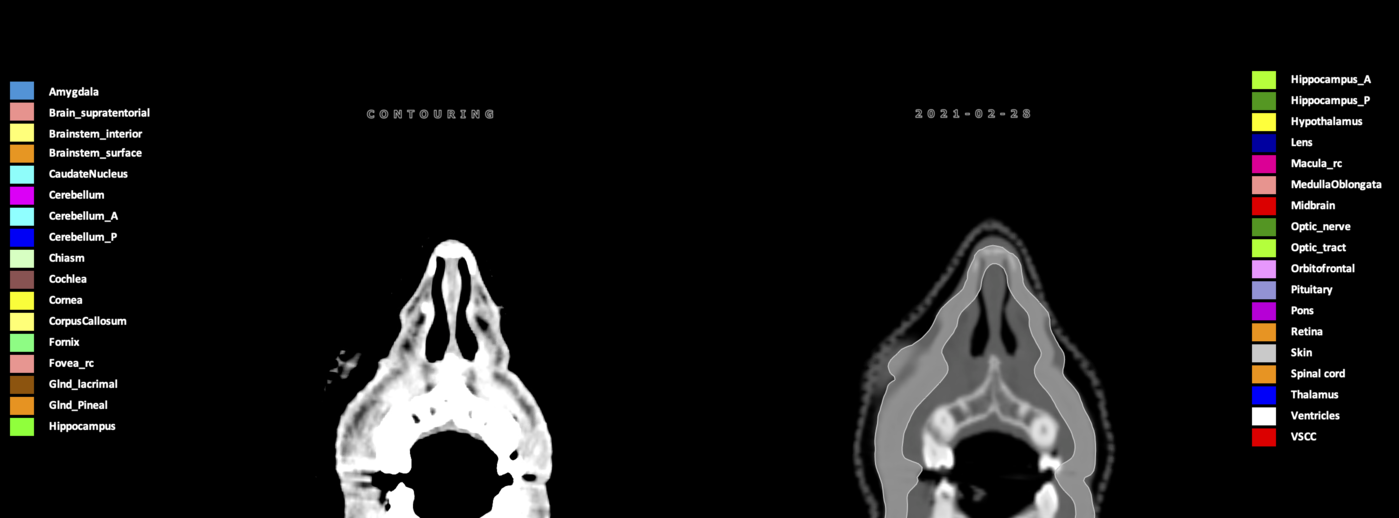

Included are all OARs known to be relevant for radiation-induced toxicity in neuro-oncology: brain, brainstem (midbrain, pons, medulla oblongata), chiasm, cerebellum (anterior & posterior), cochlea, cornea, hippocampus (anterior & posterior), hypothalamus, lens, lacrimal gland, optic nerve, pituitary, skin, and vestibular & semicircular canals. To further facilitate research on cognition, vision and radiological changes after irradiation of the brain, potential clinically-relevant OARs are included: amygdala, caudate nucleus, cerebellum (anterior & posterior), corpus callosum, fornix, macula, optic tract, orbitofrontal cortex, periventricular space (PVS), pineal gland, and thalamus.

Three-dimensional delineation of the 25 consensus OARs for neuro-oncology are shown on CT (WW/WL 120/40, 3000/600), 3T MR images, (T1Gd, T2FLAIR 1mm) and 7T MR (MP2RAGE 0.7 mm). All are presented in transversal, sagittal and coronal view.